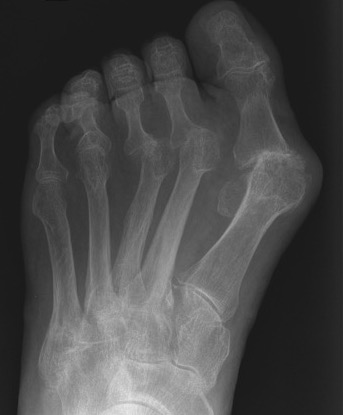

Forefoot

Great toe

Hallux valgus / rigidus

Metatarsalgia

Pathology

Synovitis of MTPJ with capsular destruction

- dorsal subluxation MTPJ

- claw toes develop (MTPJ hyperextended, PIPJ flexed)

- plantar fat pad displaced distally and metatarsal heads exposed to plantar skin